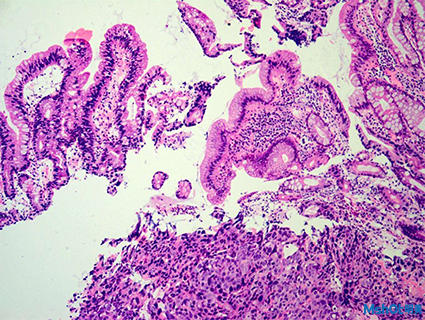

A:COVID-19肺的典型表現(xiàn);明顯增厚的肺泡間隔和充血性間質(zhì)插入,插入:詳細(xì)的視圖突出間質(zhì)充血;

B:廣泛的支氣管肺炎浸潤在一例合并化膿性肺炎的COVID-19例患者中。